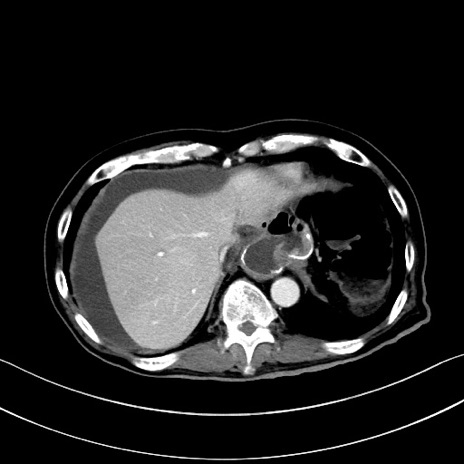

症例28(横断像)

【症例】60歳代男性

【主訴】嘔吐

【現病歴】胃癌にて胃全摘後。食思不振が悪化し、夜中に嘔吐することがある。

【既往歴】胃癌、胃全摘、脾摘、胆摘後

【データ】WBC 5900、CRP 10.56